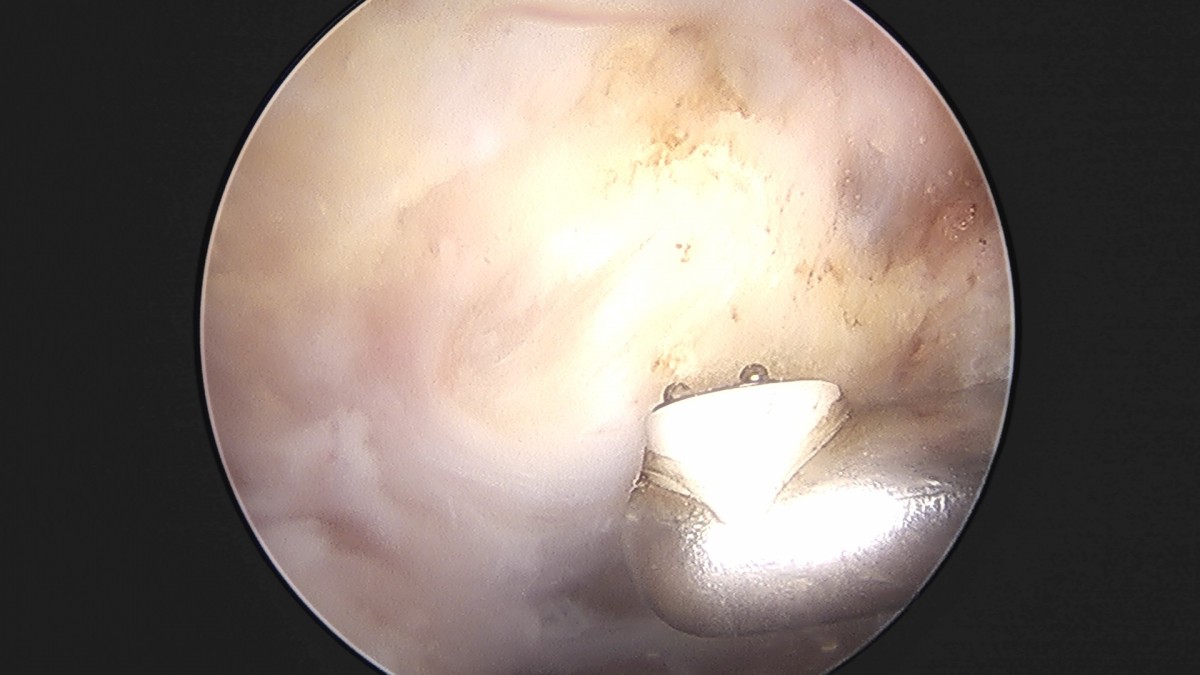

이재상원장님 어깨 견봉하 감압술 이승O 환자

작성자 최고관리자 댓글 0건 조회 806회 작성일 25-09-16 15:26